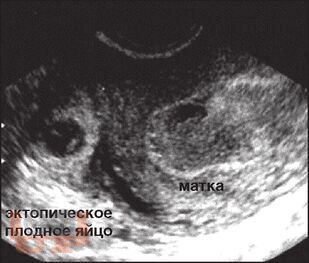

Учебно-методическое пособие посвящено вопросам диагностики и лечения внематочной беременности. Авторами составлены учебнометодические рекомендации, позволяющие в максимально короткие сроки установить диагноз внематочной беременности и выполнить соответствующий объем оперативного вмешательства. Представлены современные методы лечения при различных локализациях внематочной беременности, в том числе и редких форм.